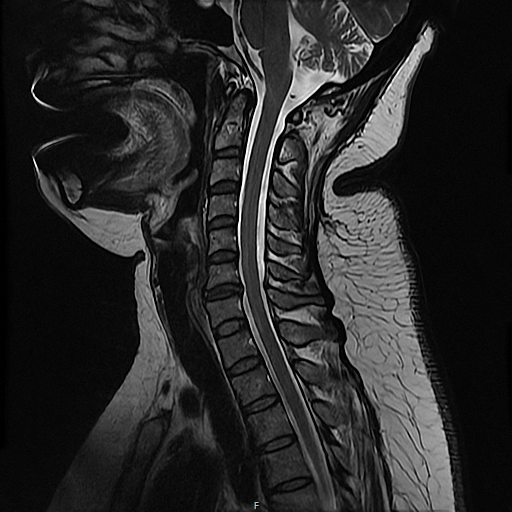

버팔로험프(버섯증후군)란?

경추 7번 부위 지방층이 섬유화되어 딱딱하게 굳는 질환

외형상 ‘버섯처럼 솟은 혹’, ‘버섯증후군’

이라도 불립니다.